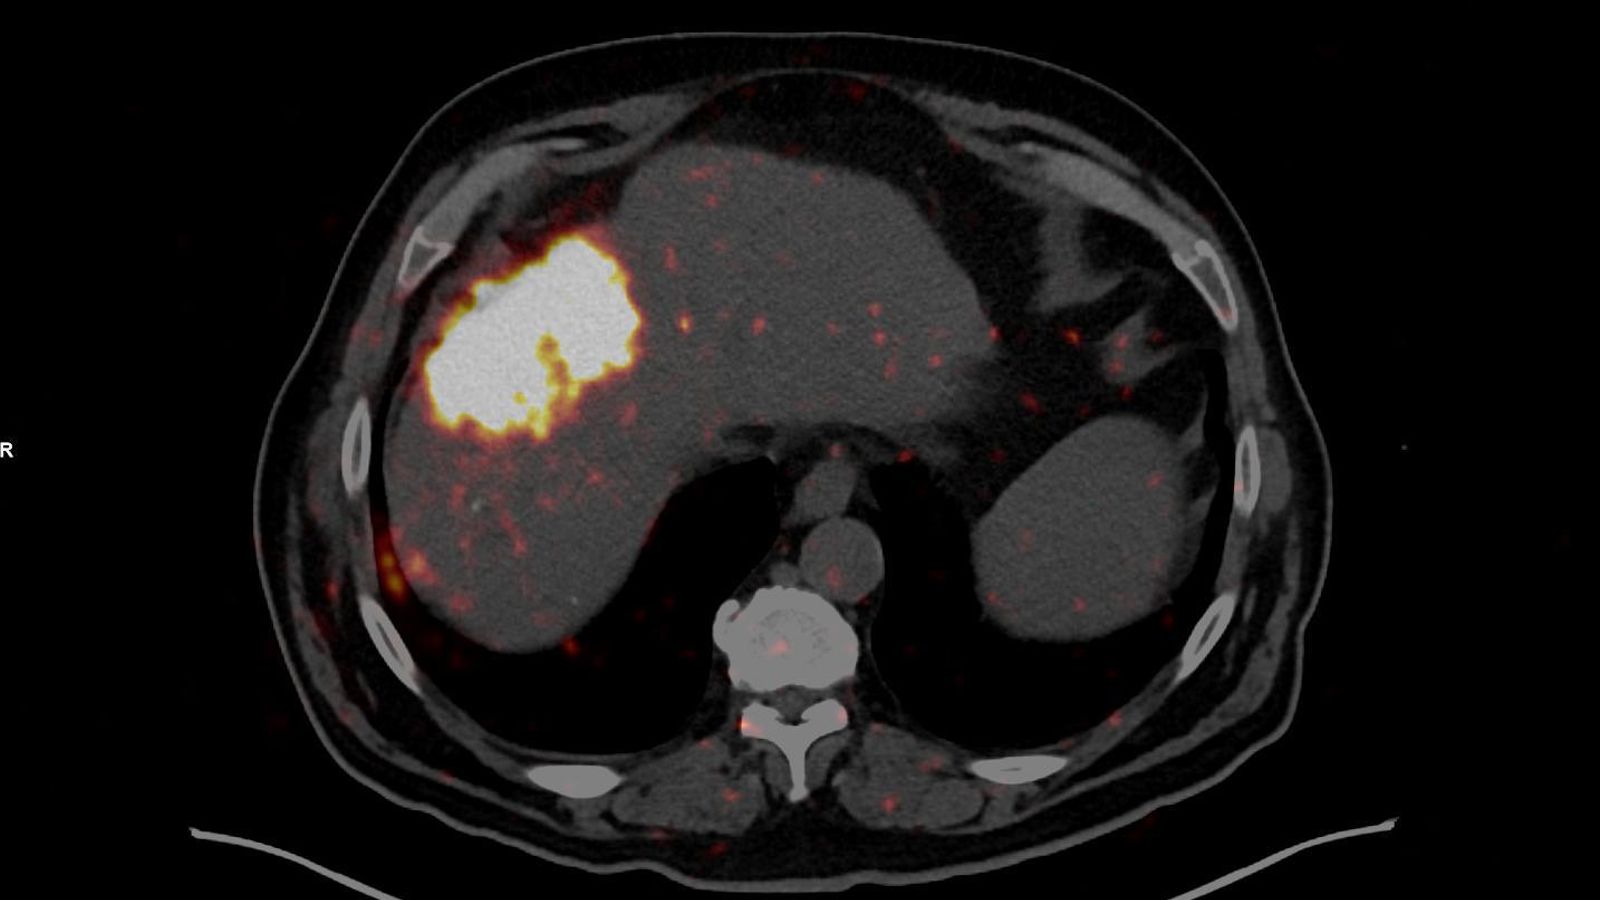

El Hospital Universitario Torrecárdenas ha llevado a cabo con éxito el primer tratamiento de radioembolización mediante microesferas muy pequeñas marcadas con Itrio-90 (isótopo radiactivo) en Almería. La intervención ha sido aplicada a un paciente con un carcinoma hepatocelular y supone un hito en la oferta de tratamientos oncológicos avanzados en la provincia.

Como han explicado desde el Servivio de Medicina Nuclear del hospital de referencia, el procedimiento ha sido el resultado de abordaje integral y coordinado entre diferentes especialidades, destacando la labor conjunta del Servicio de Medicina Nuclear y el Servicio de Radiología Vascular e Intervencionista. El jefe de Medicina Nuclear, Manuel Guerrero, explica que “el objetivo es administrar una dosis de alta radiación beta, de corto alcance (unos 2 a 4 milímetros) por la arteria hepática hacia el tumor y preservar el tejido sano circundante al tumor”. La radioembolización es un tratamiento médico que consiste en una oclusión deliberada, controlada y terapéutica de un determinado vaso sanguíneo. Las microesferas quedan atrapadas dentro del tumor y se persigue que durante unos días radie selectivamente el tejido tumoral destruyéndolo o al menos controlando su crecimiento. Es una radioactividad muy local y selectiva que se tolera muy bien y no impide al paciente estar en contacto con otras personas ni altera de manera significativa su vida diaria.

La técnica que se ha aplicado por primera vez a un paciente en el Hospital Universitario Torrecárdenas “ha demostrado muy buenos resultados terapéuticos y escasos efectos secundarios”, como ha avanzado Guerrero. Con esta intervención, el centro hospitalario de referencia en la provincia refuerza su compromiso con la innovación y la excelencia en terapia metabólica, ofreciendo a los pacientes de la provincia de Almería acceso a terapias de última generación.

La radioembolización combina la embolización con la radioterapia. Este tratamiento se realiza al inyectar en la arteria hepática unas pequeñas esferas radiactivas (microesferas) que tienen un isótopo radiactivo (itrio-90) adherido. Una vez inyectadas, las esferas se alojan en los vasos sanguíneos cercanos al tumor donde emiten pequeñas cantidades de radiación hacia el lugar donde está el tumor por varios días. La radiación se desplaza a una distancia muy corta de modo que sus efectos son limitados principalmente al tumor. La intervención del primer paciente en Almería ha resultado un “éxito”, como ha valorado el Servicio de Medicina Nuclear.